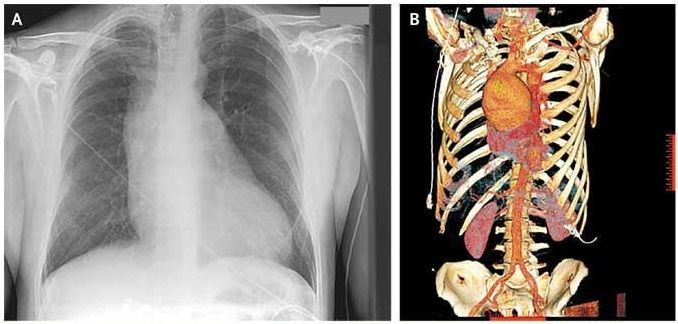

Auscultation of the precordium was notable for an aortic regurgitant murmur. Electrocardiography showed left ventricular hypertrophy. Chest radiography revealed a widened mediastinum (Panel A). 3-D reconstruction computed tomographic angiography of the chest showed a 9.5-cm ascending aortic aneurysm (Panel B).